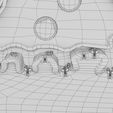

神经肌肉接头示意图